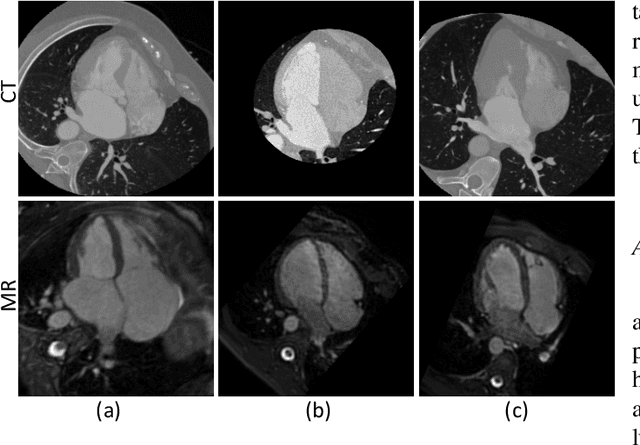

Abstract:Accurate segmentation is a crucial step in medical image analysis and applying supervised machine learning to segment the organs or lesions has been substantiated effective. However, it is costly to perform data annotation that provides ground truth labels for training the supervised algorithms, and the high variance of data that comes from different domains tends to severely degrade system performance over cross-site or cross-modality datasets. To mitigate this problem, a novel unsupervised domain adaptation (UDA) method named dispensed Transformer network (DTNet) is introduced in this paper. Our novel DTNet contains three modules. First, a dispensed residual transformer block is designed, which realizes global attention by dispensed interleaving operation and deals with the excessive computational cost and GPU memory usage of the Transformer. Second, a multi-scale consistency regularization is proposed to alleviate the loss of details in the low-resolution output for better feature alignment. Finally, a feature ranking discriminator is introduced to automatically assign different weights to domain-gap features to lessen the feature distribution distance, reducing the performance shift of two domains. The proposed method is evaluated on large fluorescein angiography (FA) retinal nonperfusion (RNP) cross-site dataset with 676 images and a wide used cross-modality dataset from the MM-WHS challenge. Extensive results demonstrate that our proposed network achieves the best performance in comparison with several state-of-the-art techniques.